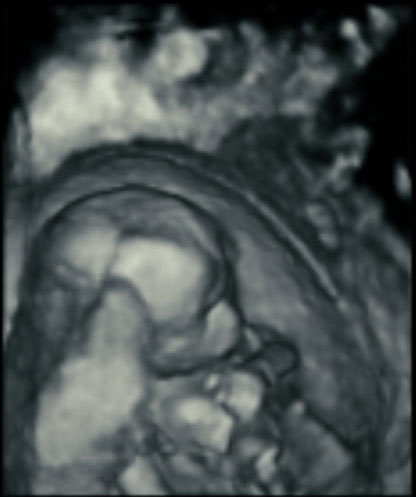

Here’s how ultrasound works in pregnancy: As early as 16 weeks, women can see a “fetal portrait” of their baby and determine its gender. Ultrasound technology has improved dramatically over the decades from flat, grainy black and white images to the current three-dimensional time experience.

Most hospitals offer some 3D scanning, but 3D ultrasound produces images that show the width, height and depth of a developing child. Rather than sending sound waves straight into the womb and recording when they bounce back as is common in 2D imaging, 3D ultrasound sends sound waves from different angles. A computer then renders a 3D image based on this data.

4D ultrasound adds movement as it occurs. The fourth dimension is time. You’re actually watching your baby live in 3D mode. How cool is that?